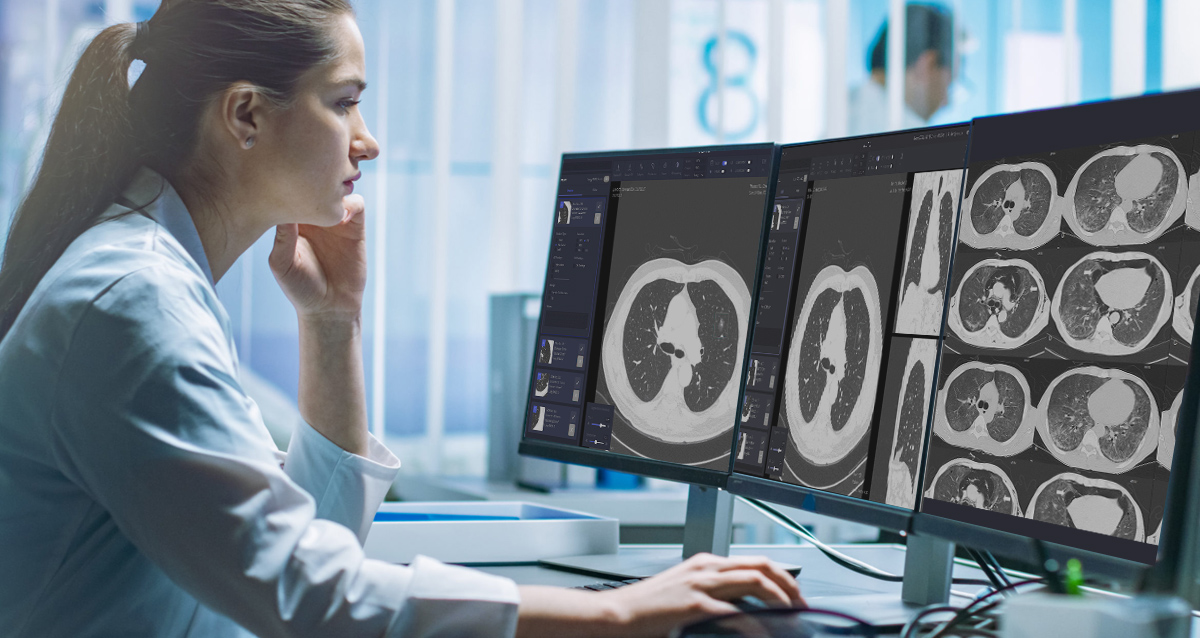

Early detection of pulmonary nodules is critical to diagnose and treat lung diseases.

It is often challenging to read hundreds of images per patient to detect nodules, analyze them and compare them over time — hence the availability of multiple software products for CT machines.

VUNO Med-LungCT’s competitive edge is about its performance. An AI-based product that assists lung diseases diagnosis, it also provides data on nodules’ size, volume, and location.

Results are integrated with PACS in the format of GSPS objects, which ensures great user convenience.